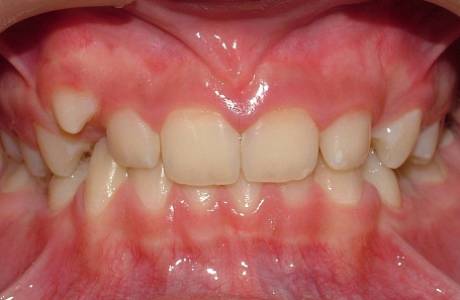

До лечения

Подросток 12 лет. Глубокий прикус, выраженный дефицит места для верхних клыков и премоляров внизу.Смещение средней линии зубов. Жалобы – «не прорезываются зубы»